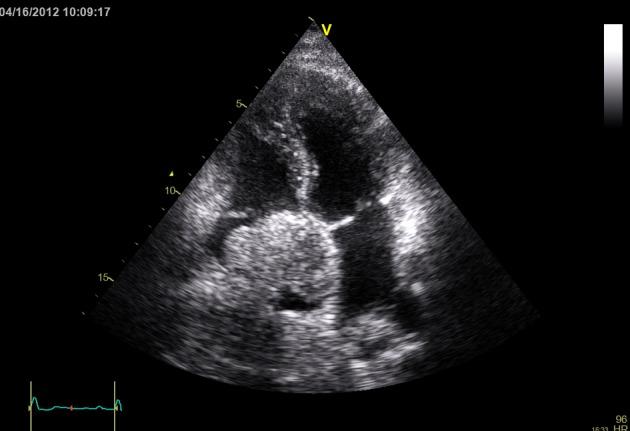

A 41-year-old man presented to the emergency room for evaluation of substernal chest pain, shortness of breath and generalized failure to thrive. Patient had history of hepatitis B and HIV. During recent evaluation of hepatic mass, patient was found to have hepatocellular carcinoma on biopsy. Patient had no history of cirrhosis of the liver in the past. On Echocardiogram patient was noted to have a large mass filling the right atrial cavity. CT scan of abdomen, pelvis and chest showed a diffusely enlarged heterogeneously enhancing liver consistent with large hepatoma, with portal venous and hepatic vein thrombosis. Tumor thrombus extended through the hepatic veins and upper inferior vena cava into the right atrium. There was 6 cm greatest diameter enhancing mass in the right atrium. Patient had primary hepatocellular carcinoma with extensive invasion into vascular structures. His prognosis was poor and patient opted for palliative care only. In conclusion, patients with co-infection of HIV and Hepatitis B are at risk of developing hepatocellular carcinoma with extension into the right atrium and physicians managing these patients should have high suspicion of right atrial involvement with tumor extension and low threshold to order a screening echocardiogram.

一名41岁男性因胸骨后胸痛、呼吸急促和全身发育不良前来急诊室就诊。患者有乙肝和艾滋病毒感染史。近期在评估肝脏肿块时,活检发现患者患有肝细胞癌。患者既往无肝硬化病史。超声心动图显示患者右心房腔内有一个大肿块。腹部、骨盆和胸部的CT扫描显示肝脏弥漫性肿大,强化不均匀,符合大肝癌表现,伴有门静脉和肝静脉血栓形成。肿瘤血栓通过肝静脉和上下腔静脉延伸至右心房。右心房内有一个最大直径为6cm的强化肿块。患者患有原发性肝细胞癌并广泛侵犯血管结构。他的预后很差,患者仅选择了姑息治疗。总之,艾滋病毒和乙肝合并感染的患者有发生肝细胞癌并延伸至右心房的风险,治疗这些患者的医生应高度怀疑肿瘤延伸累及右心房,并应积极进行筛查超声心动图检查。